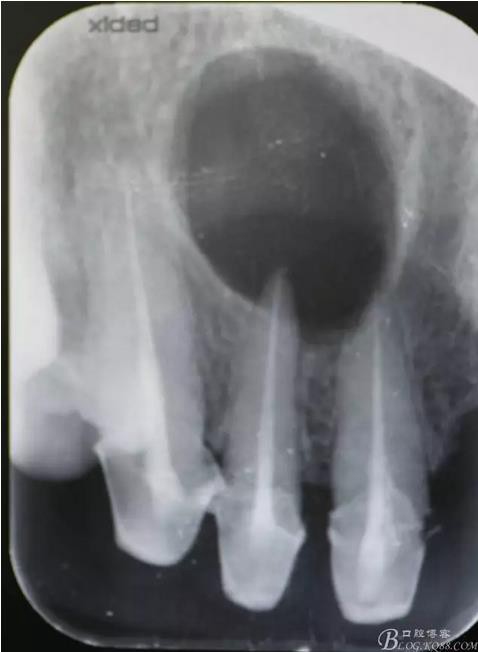

圖1.術(shù)前的根尖片影像檢查:11、12根管治療不完善